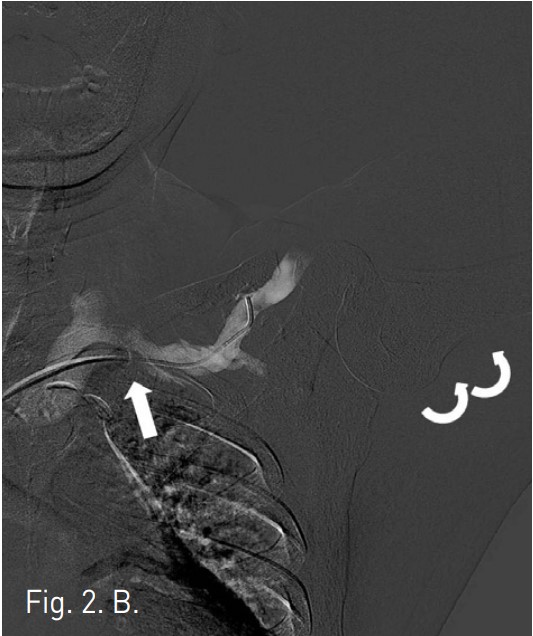

CT에서 left subclavian vein이 subclavius muscle과 anterior scalene muscle 사이에서 좁아져 있는 것이 관찰된다(Fig. 1). 팔을 내리고 시행한 venogram에서 subclavian vein이 막혀 있고 wire가 통과하지 않았으나(Fig. 2A), 팔을 머리 위로 올리고 시행한 venogram에서 subclavian vein의 distal portion이 관찰되고 catheter가 통과되었다(Fig. 2B).

Fig. 2. B

B. Subsequent subclavian venogram with the arms raised shows focal opacification of occluded subclavian vein(straight arrow) and the catheter was passed through the lesion.